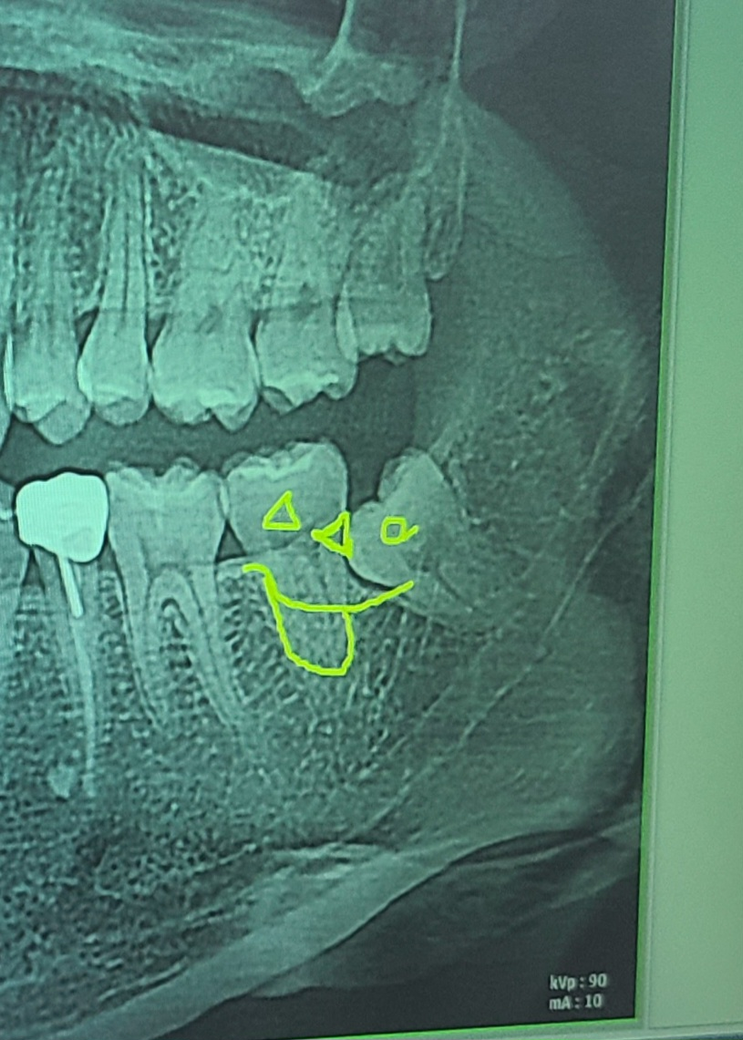

사랑니 뽑아야 될까요? (x-ray 사진있음)

사진은 왼쪽 사랑니 위아래 사진입니다

어제 오른쪽 사랑니가 아파서 발치한 후에 왼쪽 사랑니 위아래도 발치해야겠다고 의사선생님께서 말씀하셨습니다

• 1번 째 사진